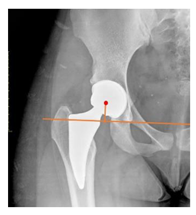

| Acetabular depth/width ratio | The width is a line connecting the superolateral edge and the inferomedial edge of the acetabulum. The perpendicular line from the latter to the deepest part of acetabulum is the depth. The ADWR is the percentage of depth to the width [25] | >38% | ![]() |